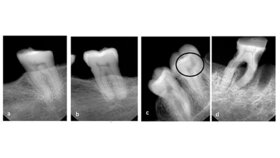

Fazit: Zusammenfassend wirkt sich ein ausreichender Vitamin D-Status positiv auf die Mundgesundheit aus und genügend UVB-Strahlung kann das Risiko von Parodontalerkrankungen verringern. Ein niedriger Vitamin D-Spiegel wird meist durch eine zu geringe Sonnenexposition verursacht und geht häufig mit Zahnfleischentzündungen, Zahnverlust und Attachmentverlust einher.